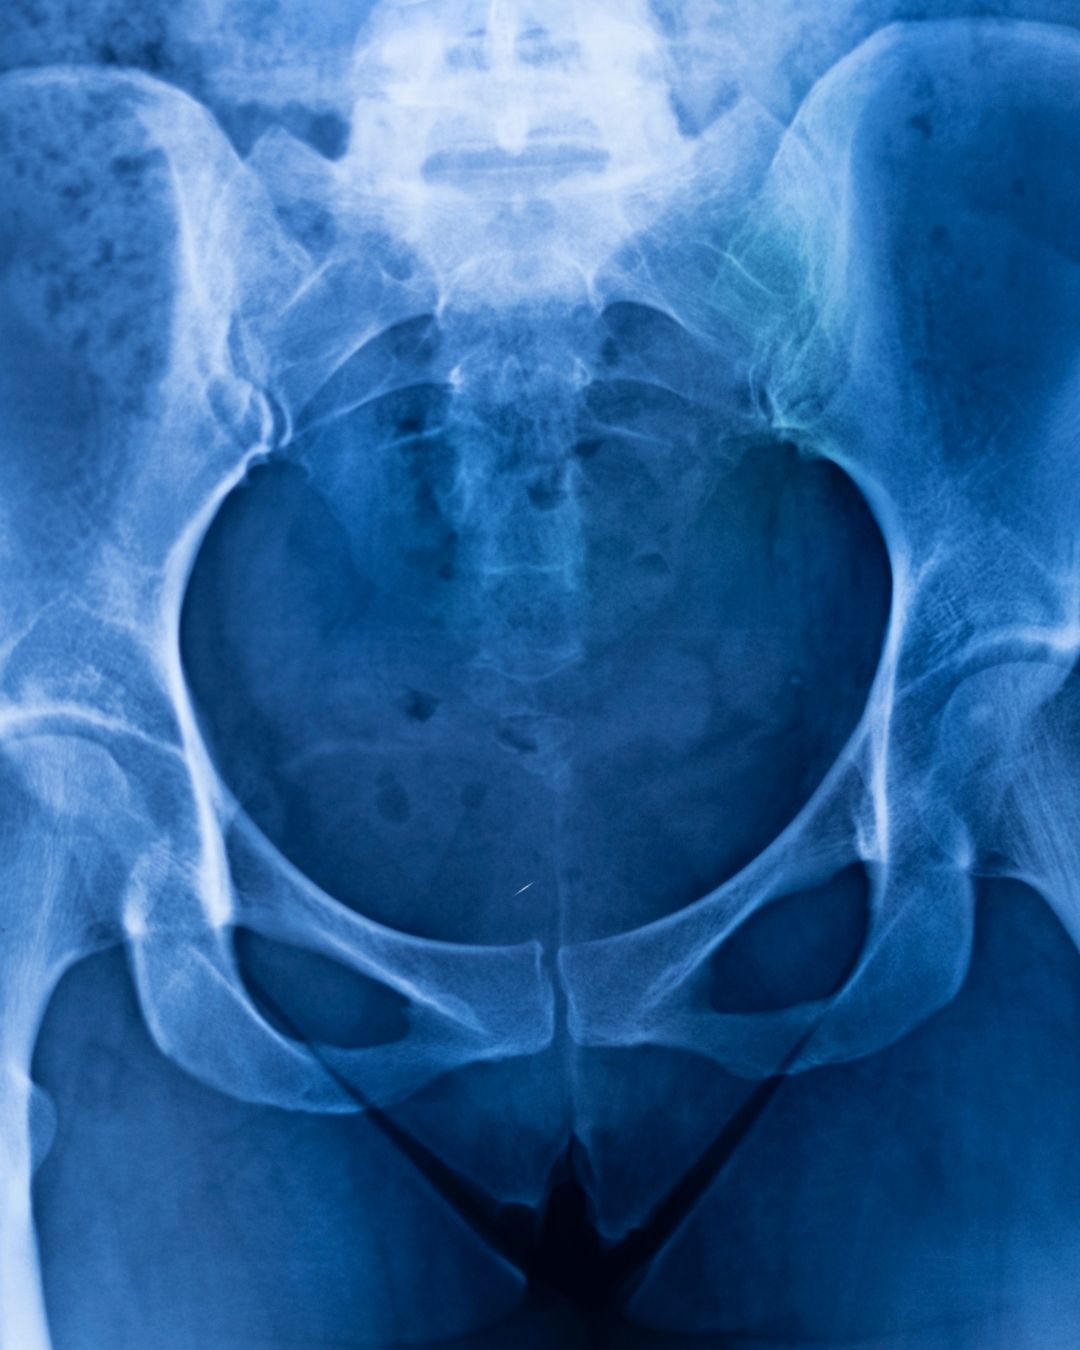

Kalça MR (Pelvis) (Tek Taraflı) NEDİR? Kalça MR’ı, manyetik rezonans görüntüleme (MR) teknolojisi kullanılarak kalça ekleminin ve çevresindeki dokuların detaylı şekilde incelenmesi işlemidir. “Pelvis” ifadesi, kalçayı çevreleyen kemik ve yumuşak dokuların da görüntülendiğini gösterir. “Tek Taraflı” ifadesi ise, sadece sağ veya sol kalçanın incelendiğini belirtir.

Özetle, Kalça MR (Pelvis) (Tek Taraflı), sadece bir kalçayı ve çevresindeki kemik ve yumuşak dokuları detaylı şekilde inceleyen, radyasyon içermeyen bir görüntüleme yöntemidir.